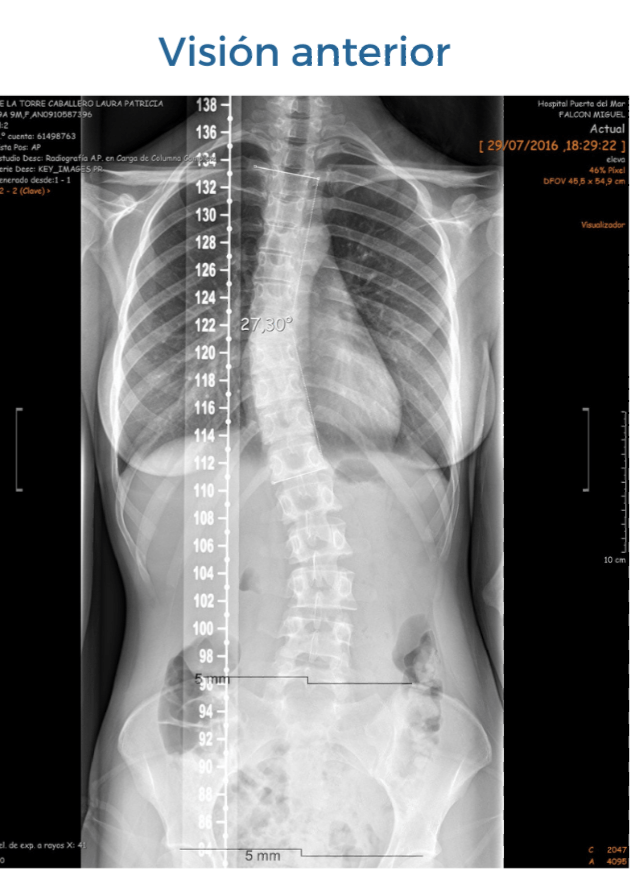

Las apófisis espinosas de las vértebras (visión posterior) rotan hacia la concavidad de la curva, salvo en un porcentaje muy pequeño "escoliosis atípica" en las que rotan hacia la convexidad. En esta rotación vertebral se ven implicadas las costillas que articulan con las vértebras y que las acompañan en esta rotación.

TOMAMOS COMO EJEMPLO UNA ESCOLIOSIS DE CONVEXIDAD DORSAL DERECHA:

Esta rotación a nivel de las últimas costillas (visión anterior) generará un adelantamiento costal bajo izquierdo y la posteriorización del derecho.

Con la pelvis pasará al contrario, la cresta ilíaca del lado izquierdo estará posteriorizada y la del lado derecho anteriorizada.